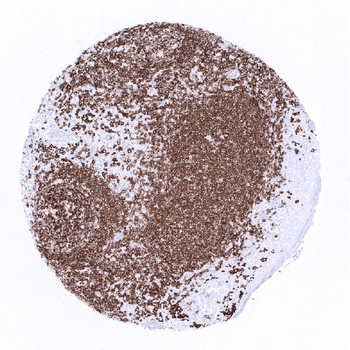

Strong CD20 staining of a germinal centre in the appendix mucosa while epithelial cells are completely negative.